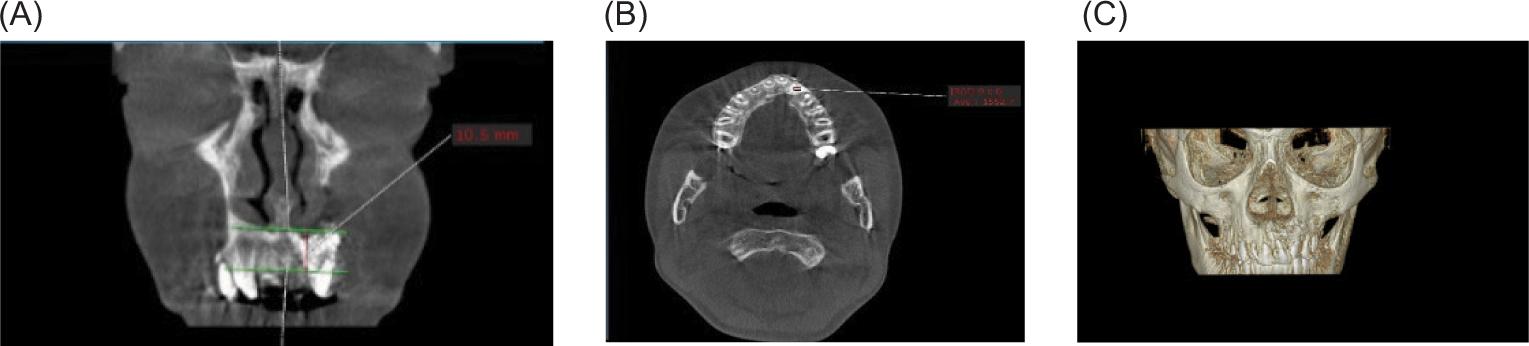

Postoperatively, the range of patient-stay in the hospital was from 1 to 2 days. Patients were instructed to remain on a fluid diet for the first 5–7 days. Antibiotics, analgesics, and mouthwash were prescribed for all patients postoperatively. Around 7–10 days after surgery, the intraoral sutures were removed. All patients in both groups underwent CBCT 6 months after the surgery to evaluate the height, bone density, and bony bridge formation at the alveolar defect. The results obtained from the two groups were compared to evaluate the effect of PRF added with bone substitute on the bone healing process. The CBCT coronal view was used to measure the height of bone formation in the 6 months after surgery for both groups. This was achieved by drawing two parallel lines, one extending from the piriform apparatus on the non-cleft side to the reconstructed piriform area on the cleft side, and the other drawn at the level of the cementoenamel junction of the central incisor, and measuring the distance between them, which represented the height of bone formation at the cleft side (Figure 4A). The axial view was used to assess the bone substitute density in the densest region in both groups 6 months after surgery by using the Hounsfield Scale (Figure 4B). The 3D view was used to assess the continuity of the alveolar bone 6 months after surgery (Figure 4C).

FIG 4. (A) Six months postoperatively, cone-beam computed tomography (CBCT) coronal view revealed bone height at the alveolar defect by drawing two parallel horizontal lines, one at the level of piriform fossa and the other at the level of the cementoenamel junction of adjacent teeth; (B) CBCT axial view used to measure bone density at the densest area 6 months postoperatively; (C) The 3D view revealed bone continuity and formation at the alveolar site.